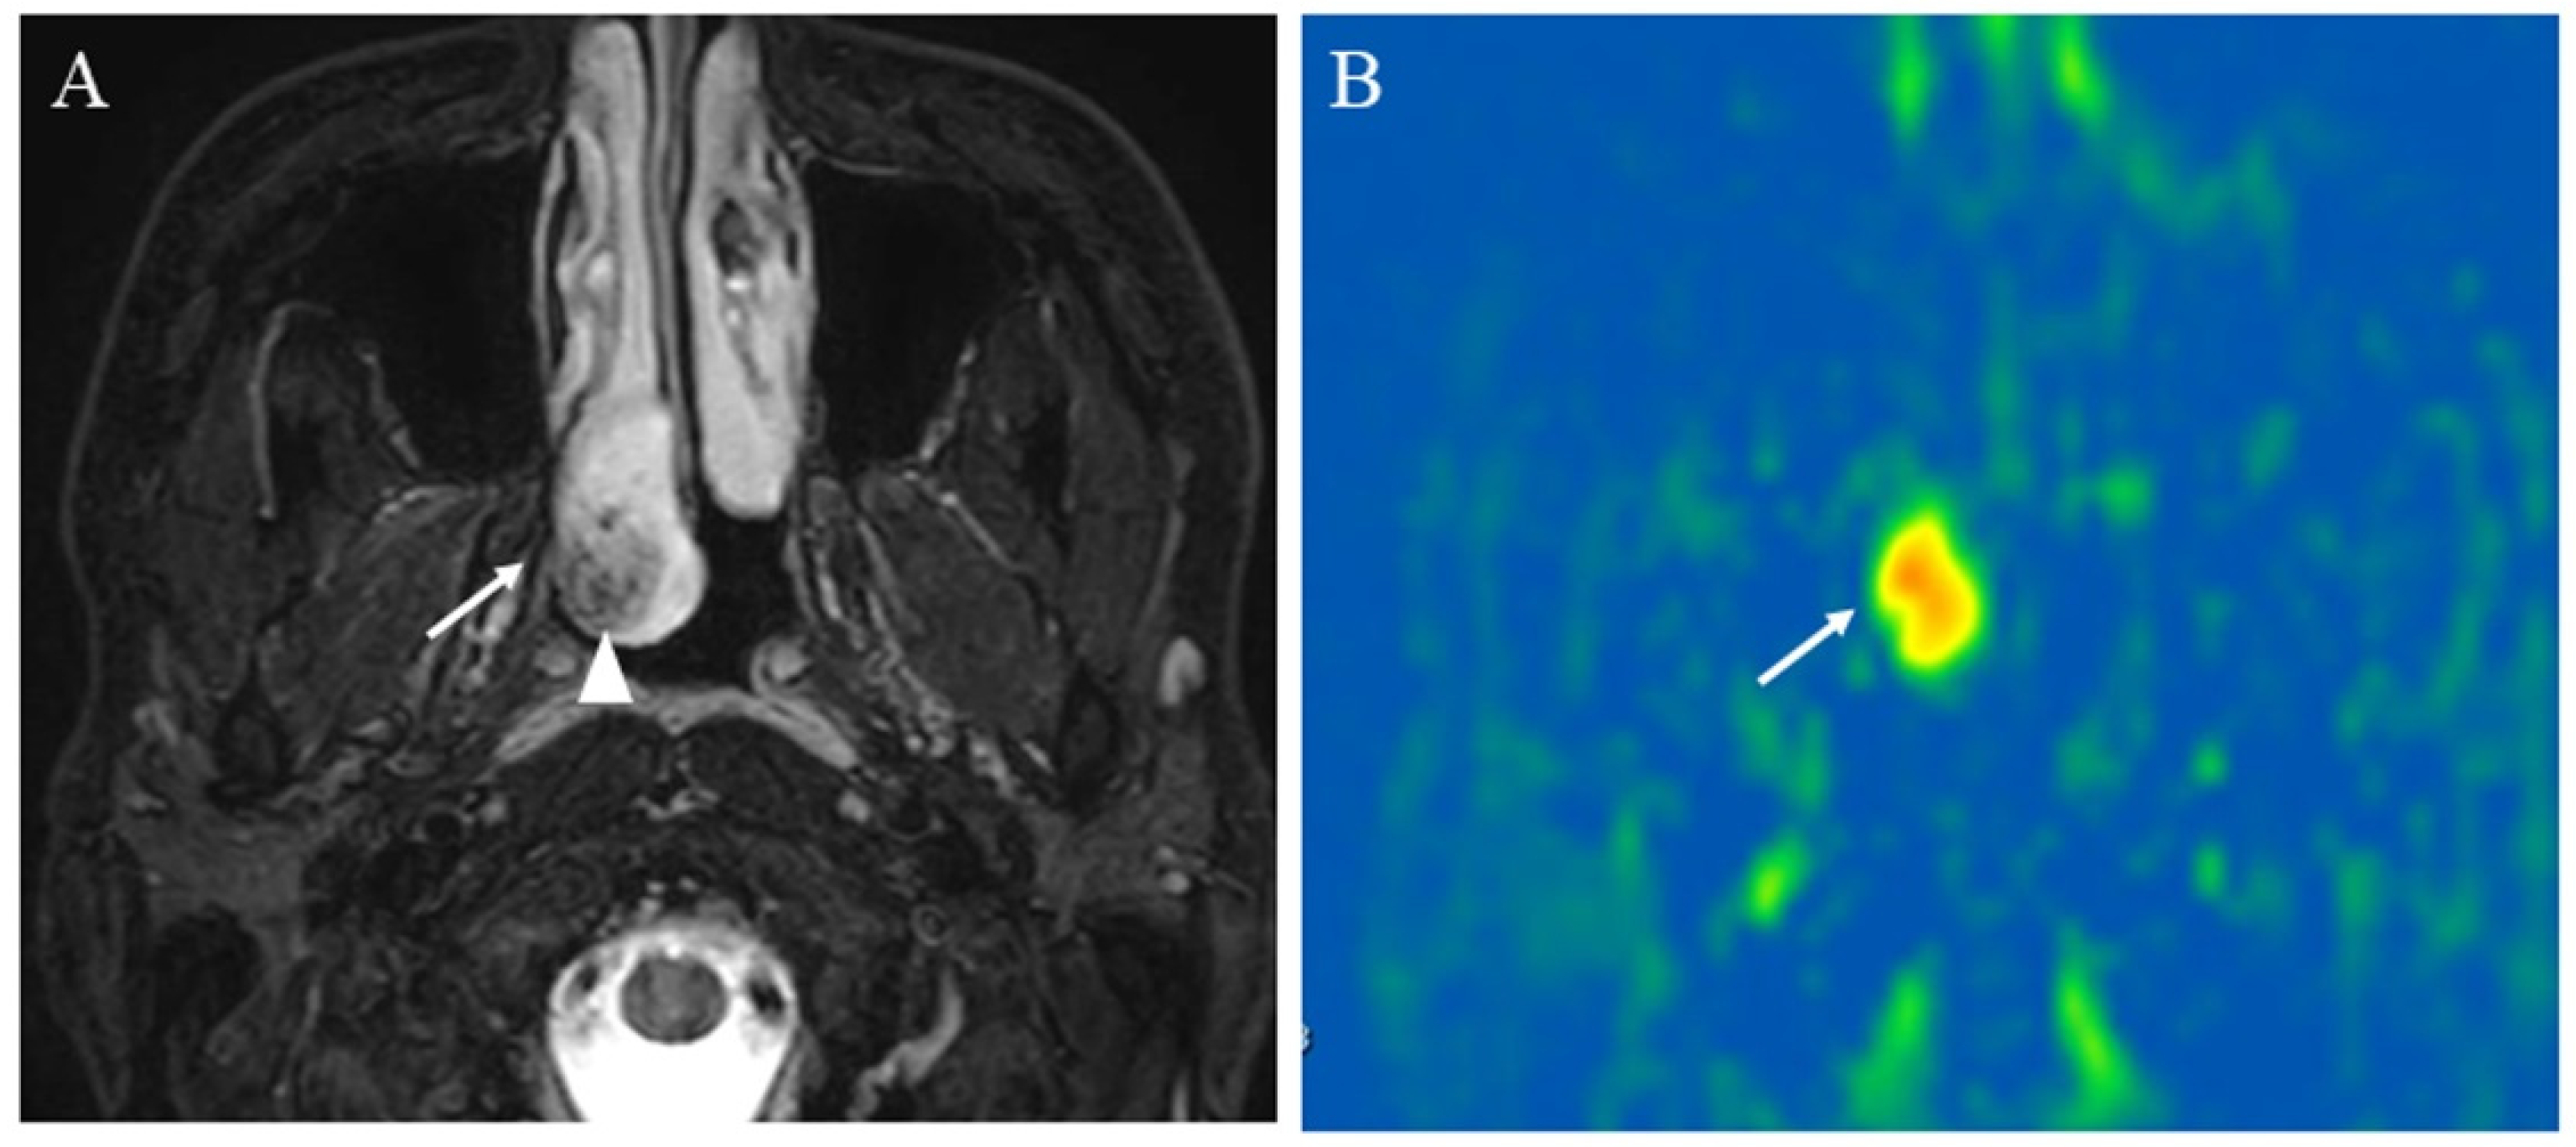

5.1.2. Hypervascular Lesions

5.1.3. Salivary Gland Tumor Differentiation: Malignant Salivary Tumors, Pleomorphic Adenomas, and Warthin’s Tumors

5.1.4. Other Head and Neck Tumors